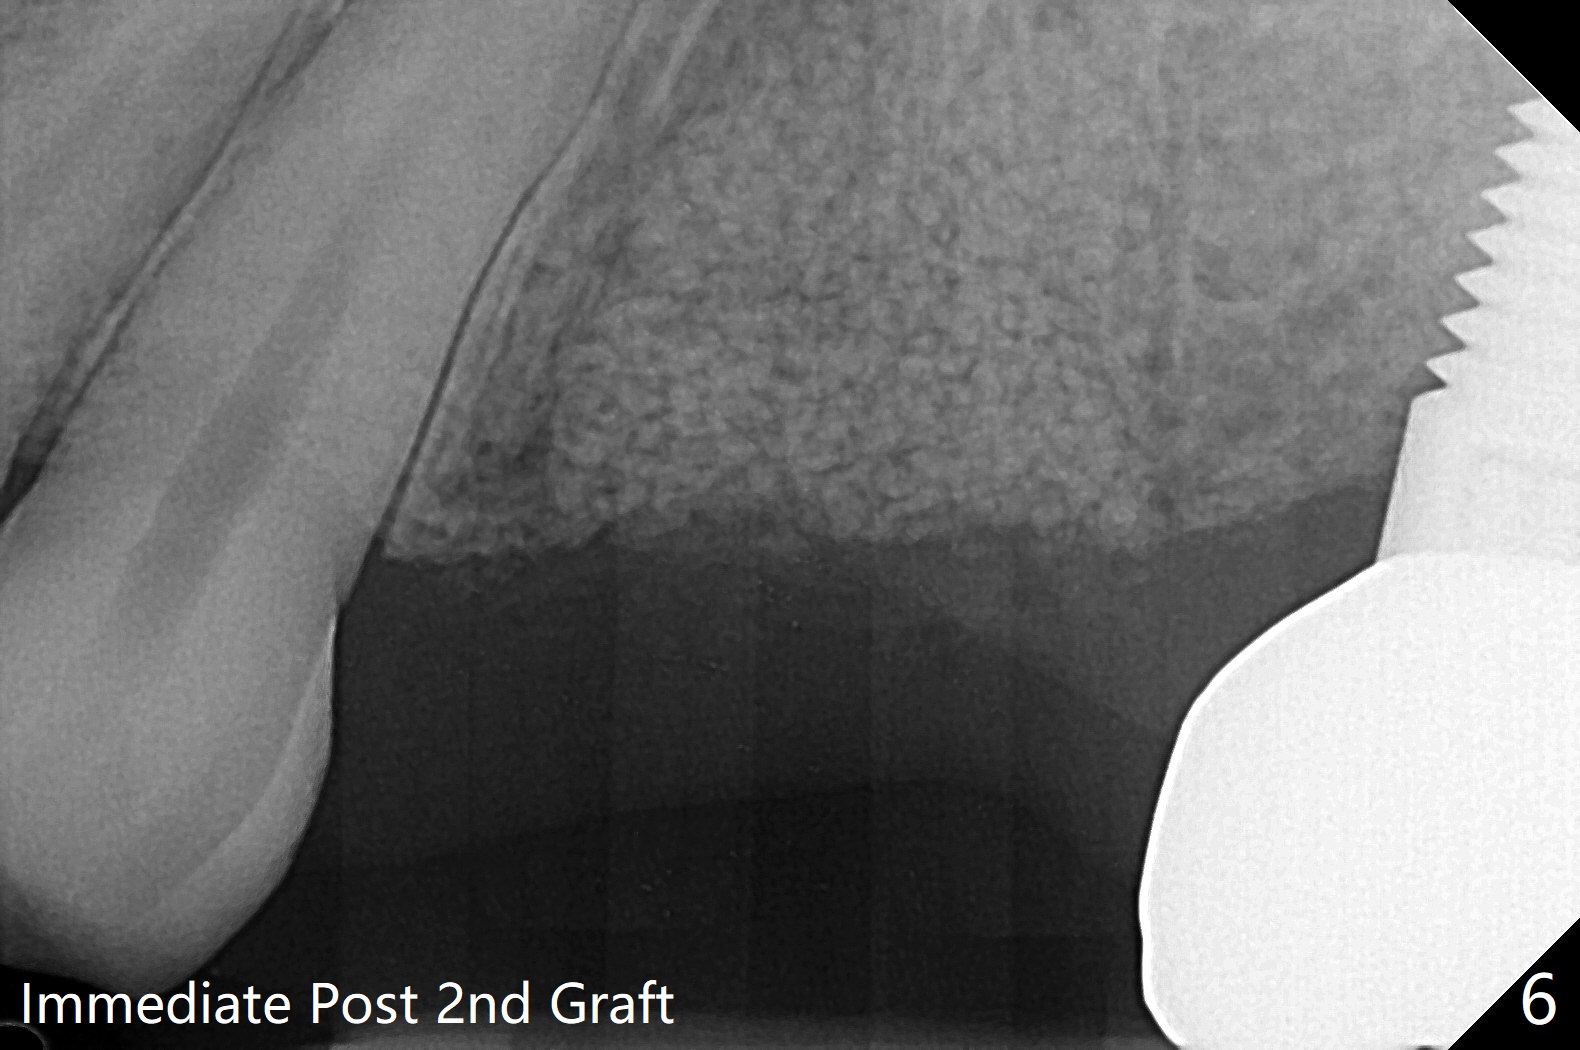

42岁女,12号牙断裂(图一),在拔除中不幸损伤13号牙,一起拔除,用GEM21S与异体骨和人工骨进行位点保存,术后骨粉一直脱落,病人觉得伤口有臭味。术后16天根尖片显示骨粉仍在牙槽窝(图二),伤口尚未愈合(图三),骨粉密度不高(图四,五)。讨论后,决定去除余留骨粉,重新刮拔牙槽窝,反复冲洗,最好放置粘性骨粉(图六),覆盖PRF和不可吸收膜,使用PTFE缝线,树脂敷料。术后三周膜和骨粉仍在原位(图七,八)。为了恢复龈乳头,术后四,五个月,利用导板去除两个牙位牙槽嵴骨质(图九),把植体植入牙槽嵴深部,之间便形成突起的牙槽嵴(图十:C)以及龈乳头。植牙整合后,利用临时牙冠,反复调整,挤压形成比较正常龈乳头。